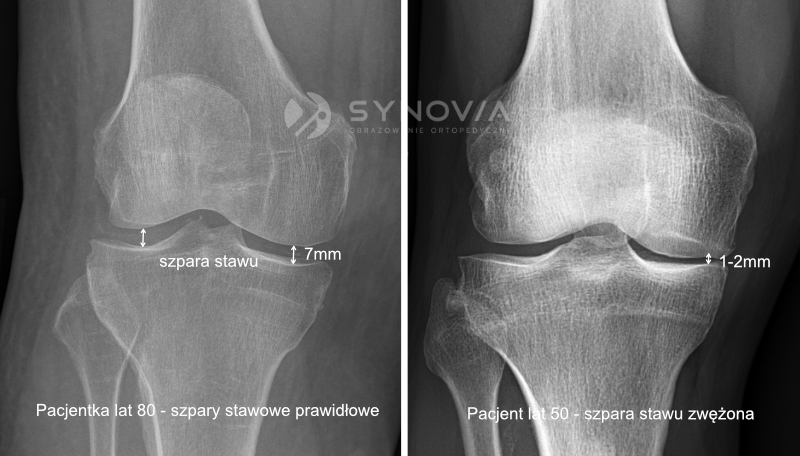

W procesie chorobowym, takim jak choroba zwyrodnieniowa stawów (osteoartroza), stężenie kwasu hialuronowego w płynie stawowym ulega znacznemu obniżeniu.

Zmniejsza się również jego masa cząsteczkowa, co przekłada się na pogorszenie właściwości mechanicznych płynu stawowego. Staw traci swoją naturalną ochronę, co prowadzi do nasilenia bólu, uczucia sztywności i ograniczenia ruchomości.

Wczesnymi i umiarkowanymi zmianami zwyrodnieniowymi stawów – najczęściej dotyczy to stawu kolanowego, biodrowego i skokowego. Terapia jest szczególnie skuteczna we wczesnych stadiach choroby, zanim dojdzie do znacznego uszkodzenia chrząstki.

Warto zaznaczyć, że wiskosuplementacja nie jest rozwiązaniem dla każdego. W przypadku zaawansowanych zmian zwyrodnieniowych, gdy chrząstka jest już znacznie zniszczona, efektywność terapii może być ograniczona.